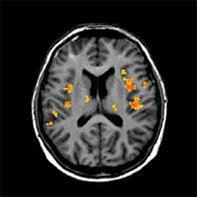

Funktionale MRT

Die MRT erlaubt die Darstellung von Stoffwechselveränderungen (MR-Spektroskopie) und spezieller Hirnfunktionen (funktionelle MRT). Neben dem Einsatz in der Hirnforschung lassen sich mithilfe dieser Methoden auch Hirnoperationen besser planen.